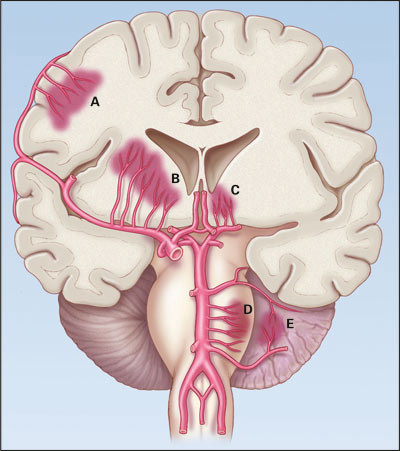

Det er vanlig å klassifisere hypertensjon både som en risikofaktor for og som en årsak til hjerneblødning. De vanligste lokalisasjoner er i striatum (særlig putamen), thalamus, pons og cerebellum (fig 1) (6). Man antar at blødninger i disse områder som regel skyldes ruptur av små arterioler, på basis av degenerative forandringer indusert av hypertensjon (6). Risikoen for residivblødning er klart korrelert til blodtrykk; 10 % per år ved diastolisk blodtrykk > 90 mm Hg og < 1,5 % per år ved diastolisk blodtrykk < 70 mm Hg (7).

Den nest hyppigste årsak er cerebral amyloid angiopati, som forårsaker såkalte lobære blødninger subkortikalt (8). Disse skyldes ruptur av små og mellomstore arterier i cortex og pia mater, med nedslag av amyloid materiale i karveggen. Amyloid angiopati ses oftest hos dem over 70 år. Lobære blødninger har en høy residivfrekvens, > 10 % per år (9).

I sjeldnere tilfeller kan blødningen knyttes til radiologisk påvisbare anomalier i blodkar. Det kan være arteriovenøse malformasjoner, aneurismer, kavernøse eller venøse angiomer og vaskulitter.

Arteriovenøse malformasjoner

Disse består i unormale karnøster der blod shuntes direkte fra arterie til vene uten å gå veien om kapillarnettet, slik at det dannes en fistel. De kan være lokalisert både nær cortex og dypt i hvit substans, og blødning fra en slik malformasjon rammer typisk pasienter under 40 år (10). Man har estimert den årlige blødningsrisikoen fra en arteriovenøs malformasjon til 2 – 4 % (10). Blødning fra en slik er assosiert med lavere morbiditet enn intracerebral blødning av annen årsak (11).

Aneurismer

Aneurismer som sprekker gir typisk subaraknoidalblødning, men kan også rumpere inn i hjerneparenkymet. Mistanke om dette bør vekkes når blødninger har kontakt med eller ligger nær arterier i hjernen, for eksempel ved lokalisasjon i fissura Sylvii nær a. cerebri media, eller i fissura interhemisphaerica nær a. cerebri anterior. Faren for ny blødning er meget stor. Aneurisme på en tilførende arterie til en arteriovenøs malformasjon er ikke helt uvanlig og kan være en krevende terapeutisk utfordring (12).